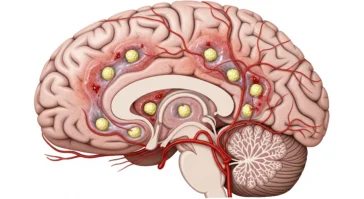

in BrainsAre Brain Tumors Genetic? Link Between DNA and Brain Cancer

When someone hears “brain tumor,” it’s totally normal to wonder, “Did this come from my family?” The honest answer is: usually, no. And that surprises a lot of people. I’ve seen families panic, digging through their family tree like detectives, only to learn that most brain tumors don’t work that way. Here’s the key idea—genetic […] More